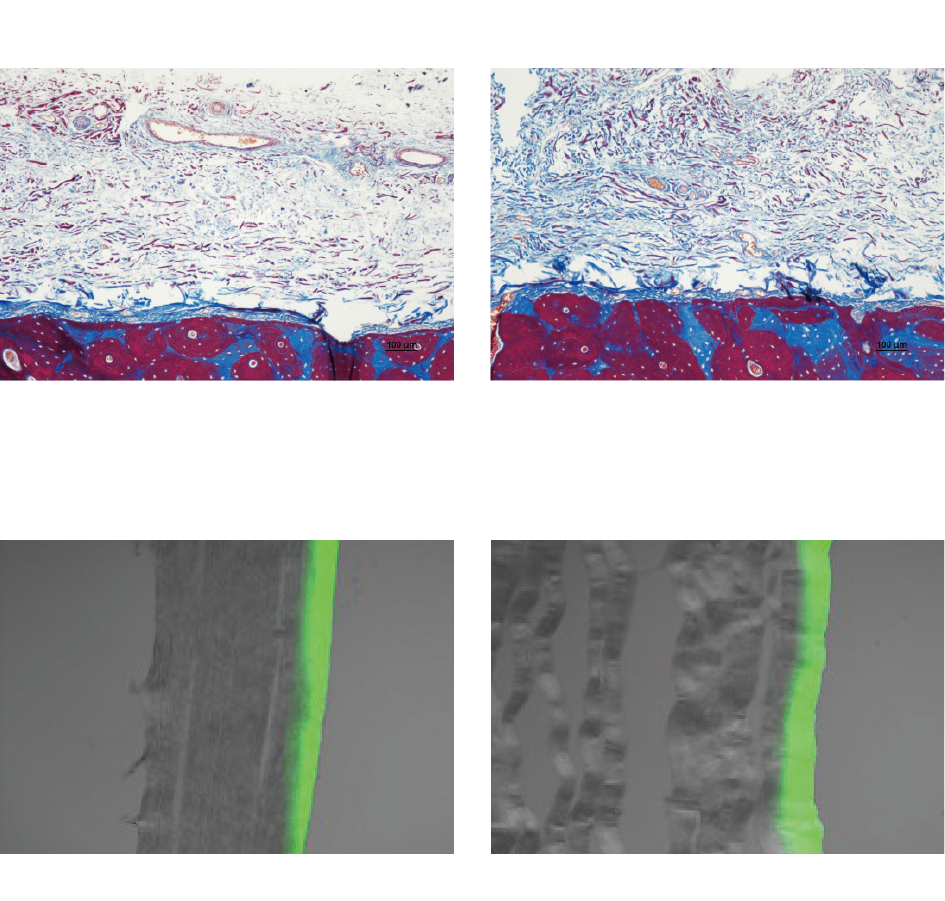

THE Cover™ is vervaardigd uit zuiver Type I collageen en kenmerkt zich door een uitstekende biocompatibiliteit en celvriendelijkheid, aangezien er geen chemische crosslinking-agenten zijn toegepast. Dit garandeert een veilige, natuurlijke integratie in het omliggende weefsel.

THE Cover™ Stiff – met verhoogde stijfheid, ideaal voor betrouwbare ruimtebehoud.